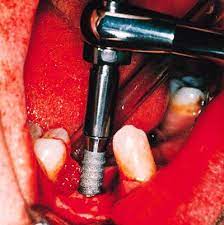

إجراءات الزراعة وما بعدها

تبدأ عملية زراعة الأسنان بتنظيف الفم وتخدير المنطقة المراد زراعة السن بها. يتم وضع الزرعات السنية بعناية ودقة،

وتتبعها إجراءات ما بعد الزراعة للتأكد من شفاء الجرح وجاهزية السن الاصطناعي للاستخدام اليومي.